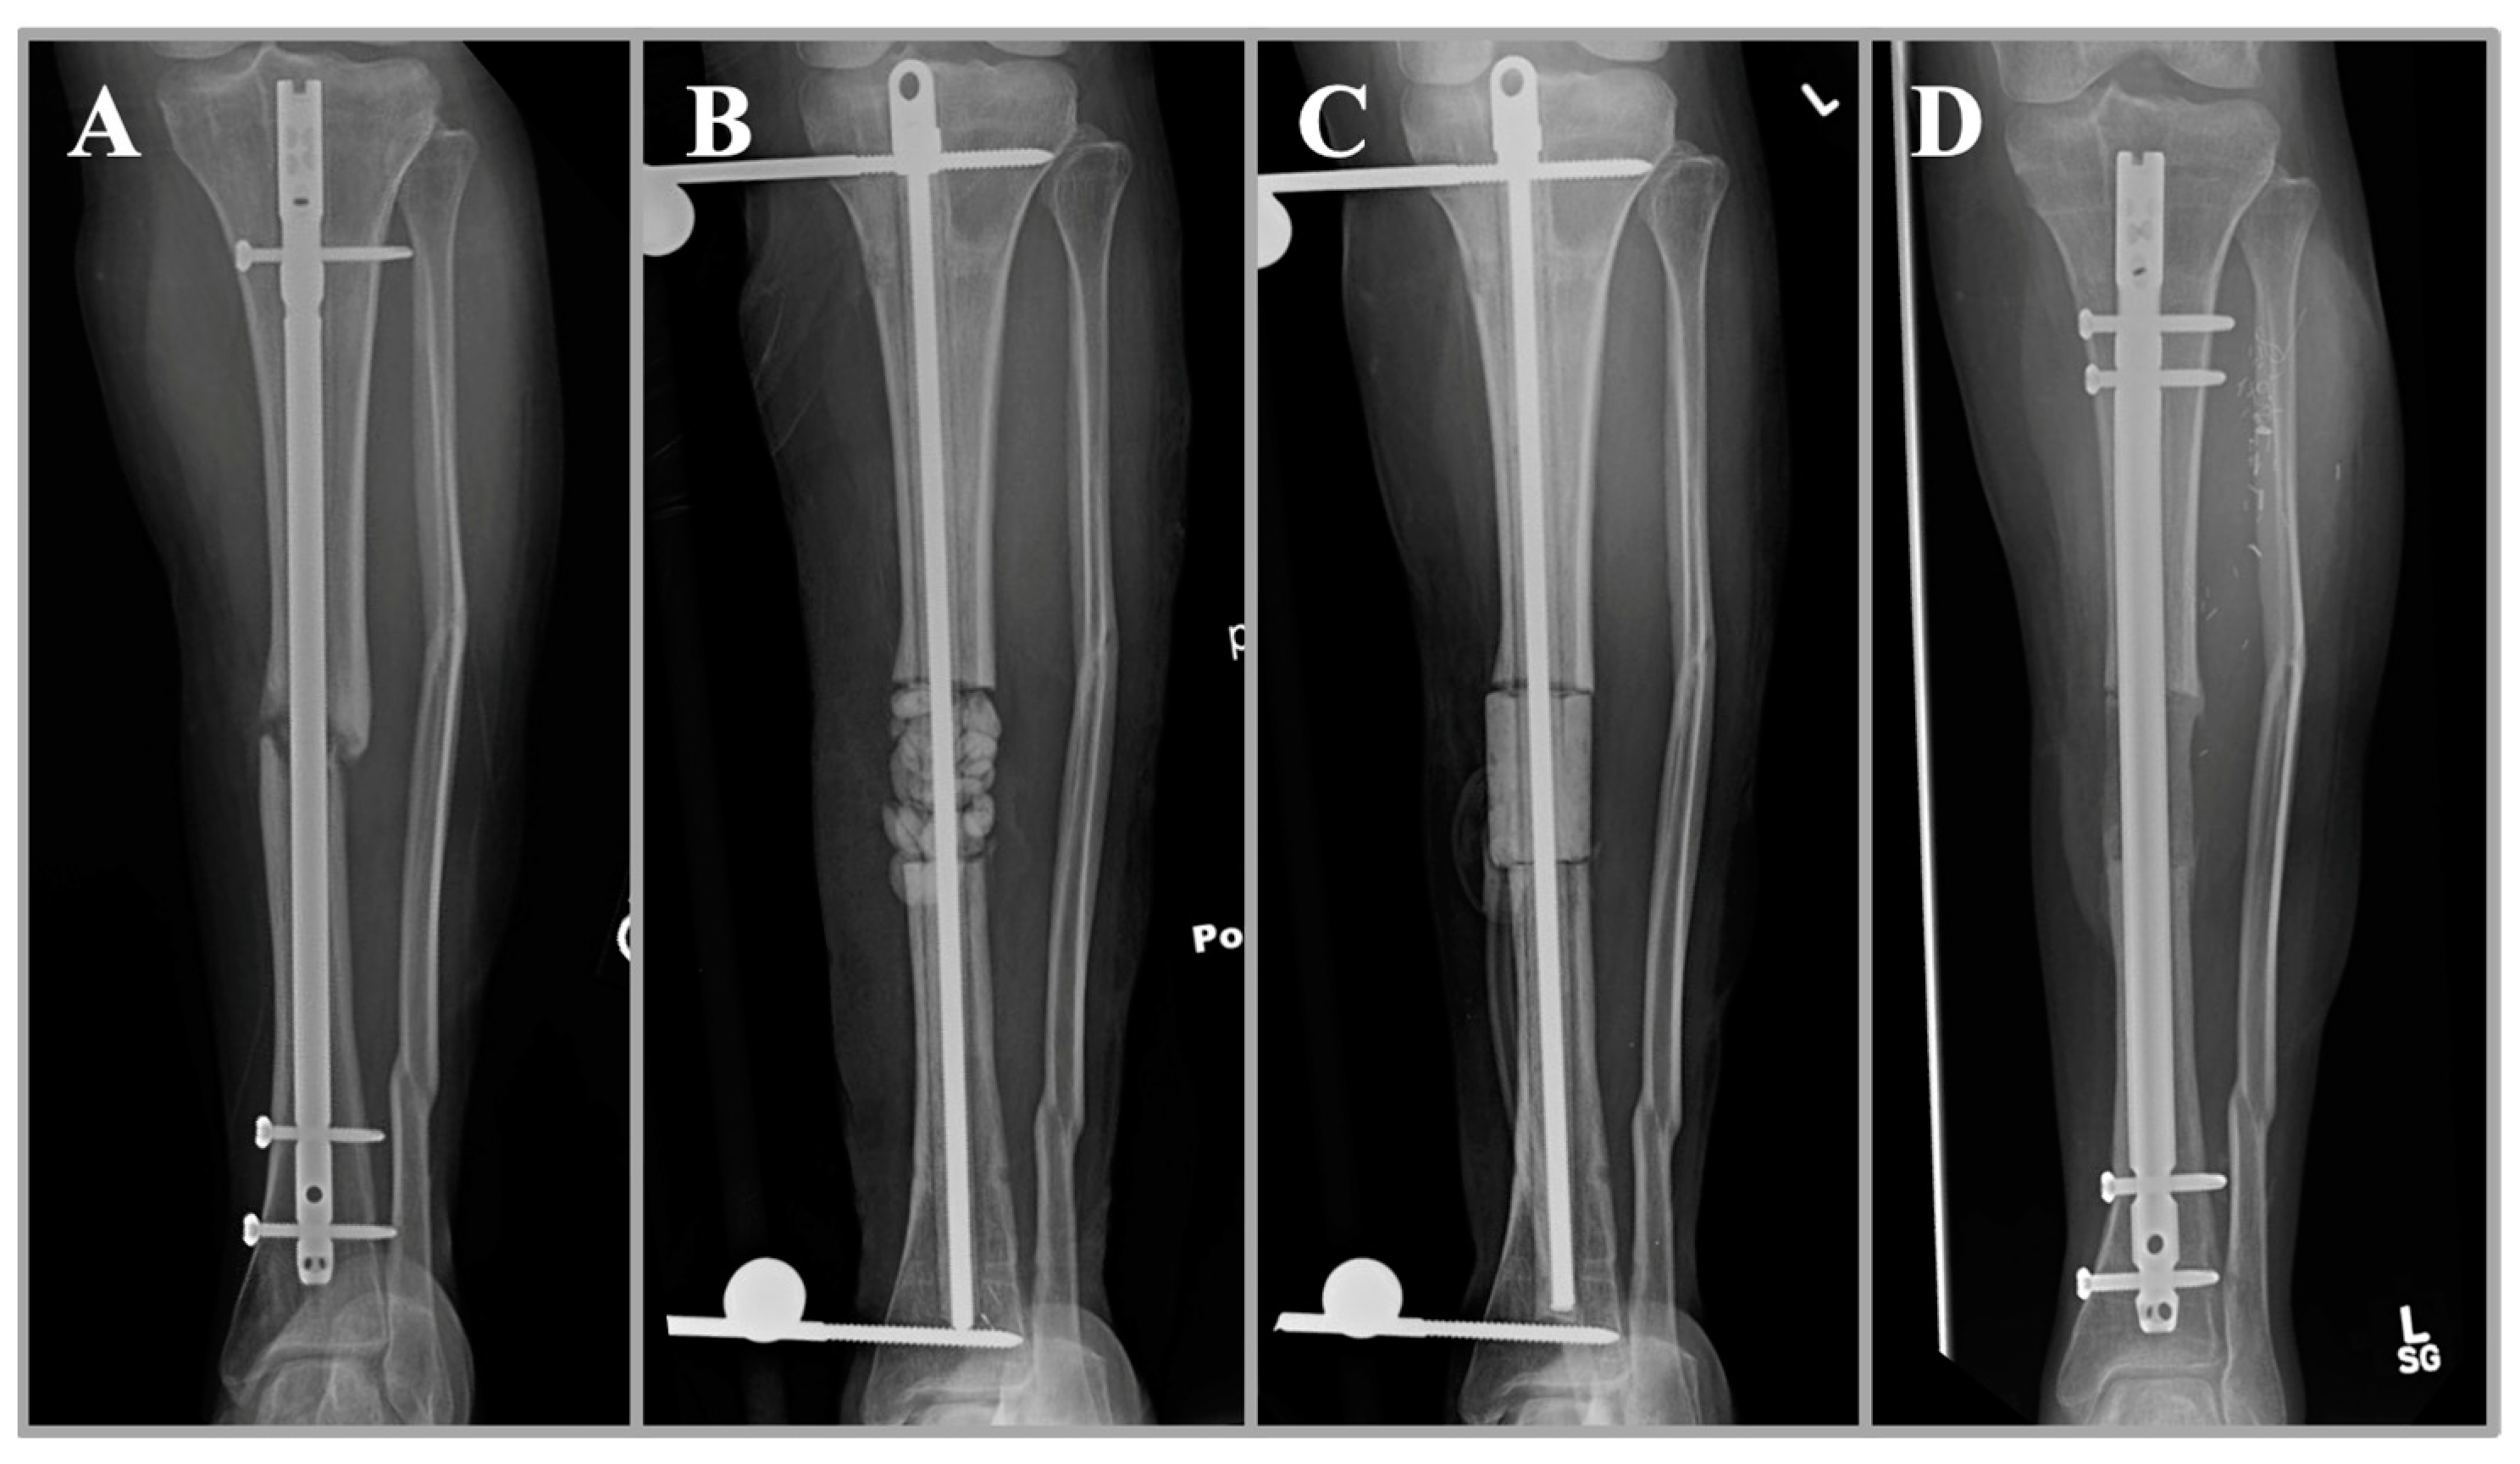

A clinical case of a 27-year-old woman with infected nonunion of the tibia after open fracture (A). She underwent initial irrigation and debridement with removal of hardware and placement of an antibiotic nail, antibiotic beads, and external fixation (B). The beads are ideal in this scenario for maximal surface area and antibiotic elution. At the same time, the antibiotic nail provides stability and local antibiotic delivery in the intramedullary space. A repeat debridement was performed with the placement of a mono-block spacer in the subsequent procedure (C). The mono-block spacer has the advantage of inducing a membrane for subsequent bone grafting and improved structural integrity. Healing of the fracture is shown after bone grafting with the placement of a new intramedullary nail (D).

Clinical images of the same patient are shown at the time of antibiotic spacer placement (A), spacer removal (B), nail placement (C), and bone grafting (D).